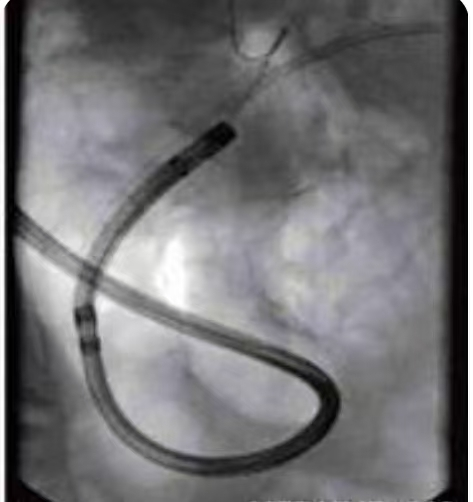

术中,两位主任默契配合,借助十二指肠镜精准定位,逐步完成胰胆管造影,清晰显示出胆管狭窄的部位与程度。随后,胆道子镜沿通道缓缓进入胆道内部,在高清直视下,结石位置、大小以及胆管黏膜状况一目了然。基于清晰的视野,主刀医师将结石击碎后逐一取出,并同步处理了胆管狭窄问题,顺利放置引流支架。

“再做一次造影复查!” 随着取石操作结束,新的胰胆管造影显示的结石无残留结果让手术室内的医护团队松了口气:整个手术过程仅耗时1小时,全程微创、出血少,患者术中生命体征平稳,术后即刻苏醒,各项指标均符合预期。